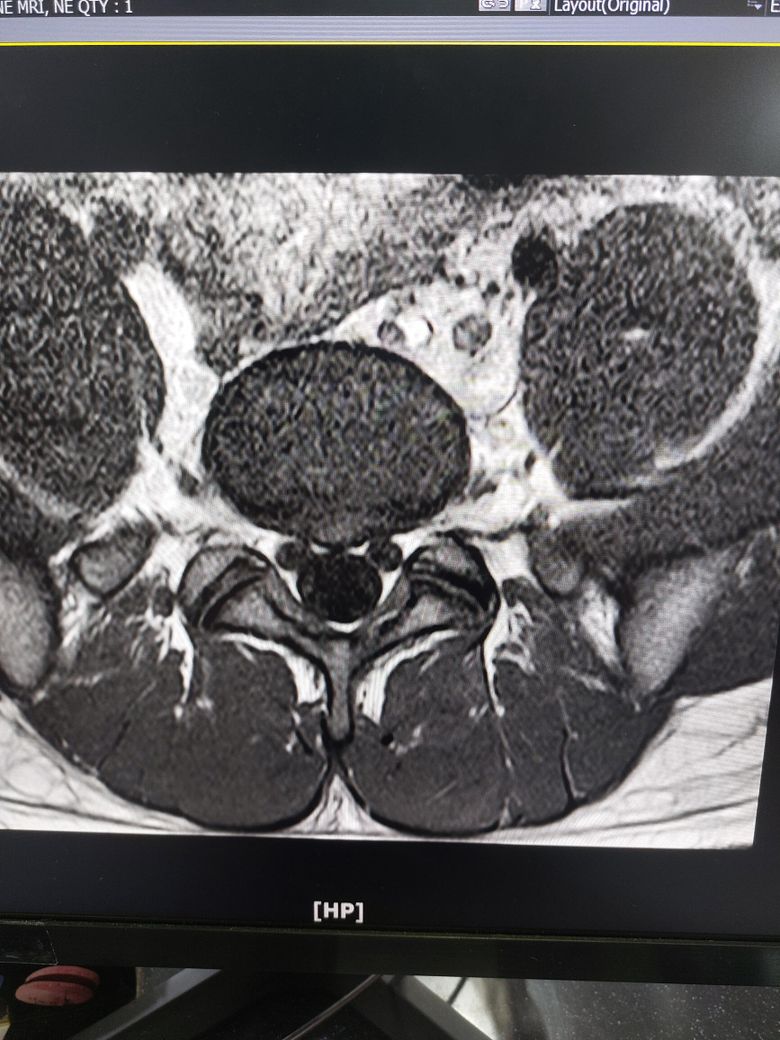

사진은 제 mri입니다